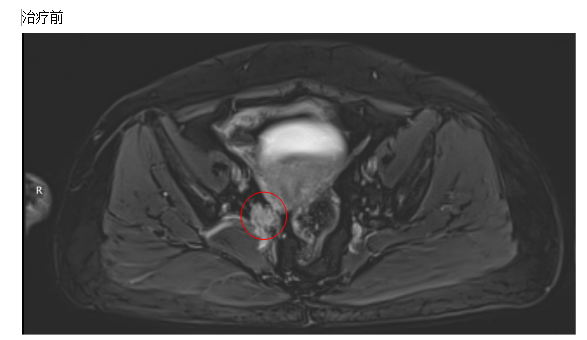

患者, 女,61岁,诊断:宫颈恶性肿瘤、鳞状细胞癌

1. 患者, 女,61岁,诊断:宫颈恶性肿瘤、鳞状细胞癌、FIGO分期:IIIC期

2.病史:患者于2024年8月1日无明显诱因出现阴道不规则流血,褐色分泌物增多,于2024.8.25就诊酒泉市人民医院,行盆腔MRI平扫提示:宫颈肿块(41mm*30mm*35mm),子宫内膜异常增厚,多考虑肿瘤性病变并侵及周缘组织可能,建议增强检查。阴道镜检查提示:宫颈呈火山口改变,组织糟脆,触及易出血。病理提示(181340):(宫颈组织)高级别上皮内病变(HSIL/CINIII级/原位癌),送检组织未见明确间质,不能除外更高级别病变,待手术标本进一步明确浸润深度。胸部CT提示:双肺多发实性小结节,建议年度复查,双肺下叶背侧少许炎性病变,右肺上叶钙化灶。建议患者住院治疗,患者及家属为进一步治疗,于2024.9.4就诊兰州市妇幼保健院,妇科超声提示:宫颈后壁占位,多考虑Ca,右侧附件区占位(0-RADS V),请结合临床。阴道镜检查所见(宫颈):未见典型宫颈形态,阴道顶端狭窄无弹性,可见一半圆形突出组织涂醋酸后;厚醋白上皮触及出血,(阴道):阴道上1/3段狭窄,挛缩白上皮粗大点状血管,上皮剥脱,出血,(外阴):发育良好,未见异常,阴道镜拟诊结果:阴道可能浸润癌,宫颈可能浸润癌?处理:阴道壁及阴道顶端组织活检。病理诊断(1579868):(阴道壁3点、5点)乳头状鳞状细胞癌,(阴道顶端赘生物)乳头鳞状细胞癌。完善相关检查后FIGO分期:IIB期,根据宫颈癌治疗指南(CSCO 2024):盆腔EBRT+近距离放疗+同步含铂类化疗(I类),遂外院分别于2024-9-6、2024-9-29日给予PC(紫杉醇240mg ivgtt d1,卡铂600mg ivgtt d1)方案化疗。遂就诊我院门诊,门诊以“宫颈恶性肿瘤”收住入院。患者自发病以来,精神良好,饮食一般,睡眠良好,大小便正常,体重无明显变化。

4. 治疗效果:

经IMRT放射放疗后,宫颈病灶较前部分缩小,宫旁淋巴结消失。